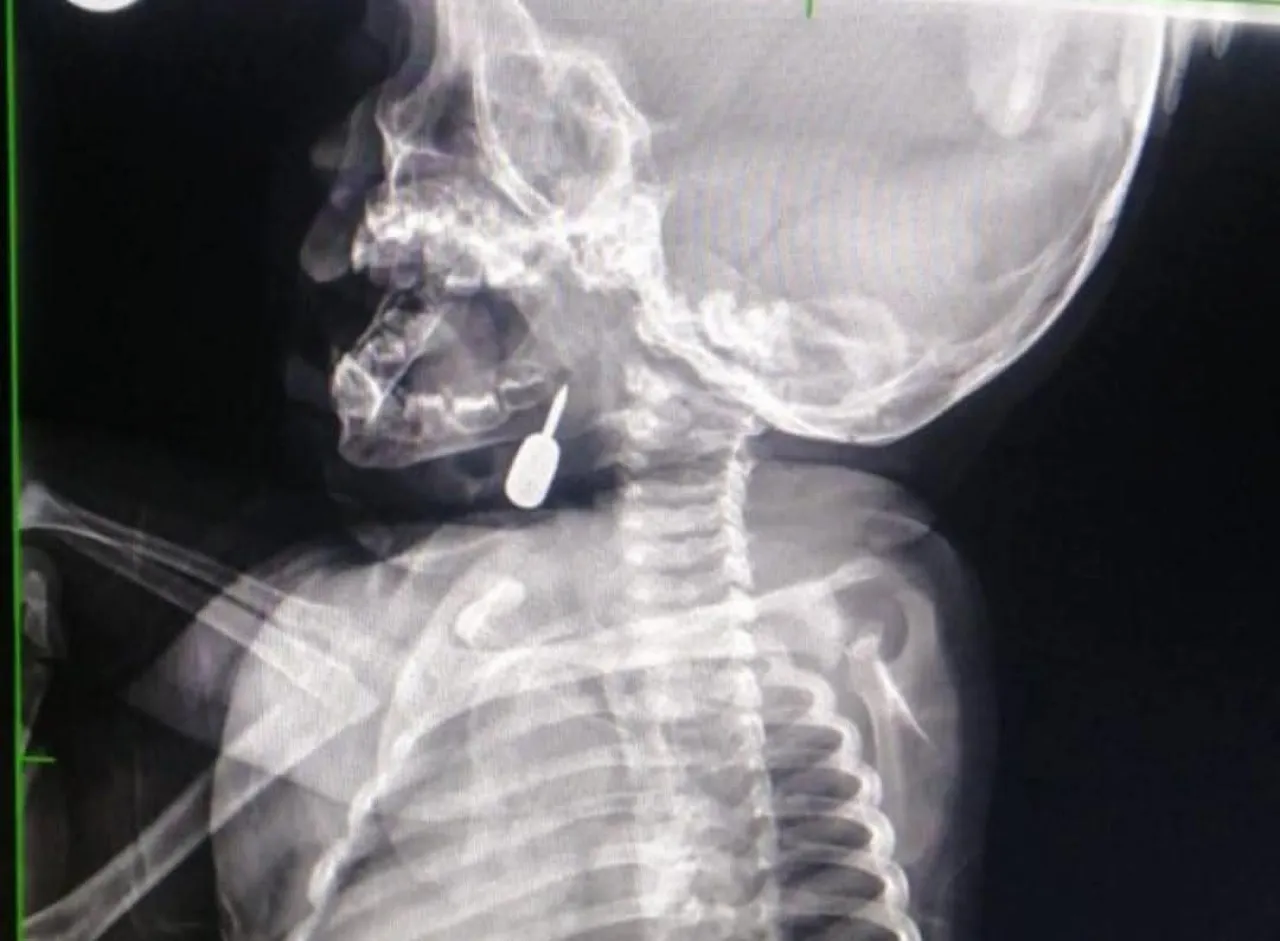

وفي تدخل طبي عاجل، أنقذ الدكتور السبول حياة طفل يبلغ من العمر أحد عشر شهراً، بعد أن وصل إلى قسم الطوارئ وهو يعاني من حالة اختناق حادة نتيجة وجود جسم معدني عالق في منطقة الحنجرة. وقد تم استخراج الجسم بنجاح، مما أسهم في إنقاذ حياة الطفل.